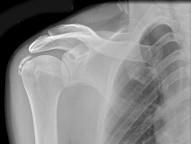

问题 男,52岁,肩痛四月余,手臂旋转时疼痛加剧,请结合影像图像选择最可能的诊断 ( )

选项 A、骨囊肿 B、骨脓肿 C、骨结核 D、冈上肌腱钙化 E、软骨瘤

答案 D